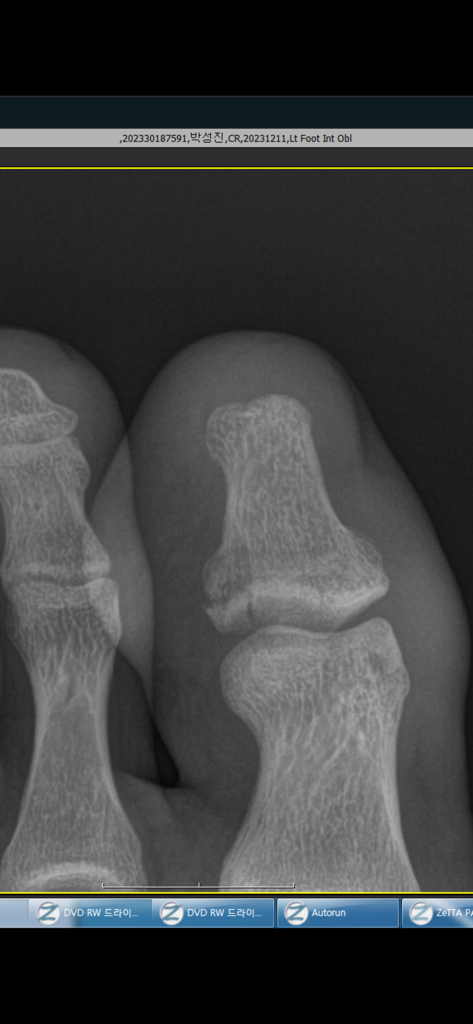

첫번째 사진이 12월11일날 찍은 엑스레이이고, 저 후에 보존적 치료릉 권하여 깁스를 했습니다. 붓기가 매우 심하여 2주뒤에 오라하셔서 2주뒤에 내원했습니다. 2주뒤인 15일에도 붓기가 심한 상태입니다. 통증도 있고

이렇게 원위지골의 전위가 발생하여 불유합 가능성이 높다고 진단을 받았습니다. 저렇게 뼈가 조각나서 전위가 발생했네요.